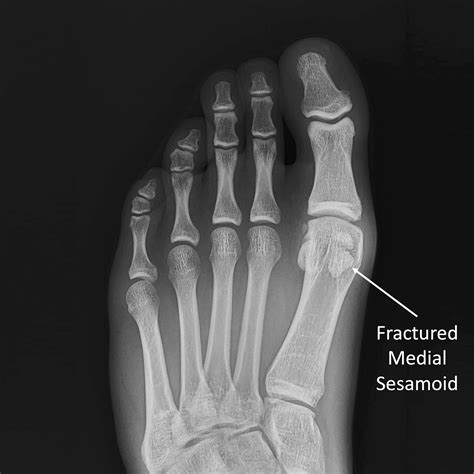

• Sesamoid Fracture: A fracture of the sesamoid bones can occur due to a sudden impact or repetitive stress. This condition is often seen in athletes and dancers.

• X-rays: To visualize the bones and detect any fractures or abnormalities.